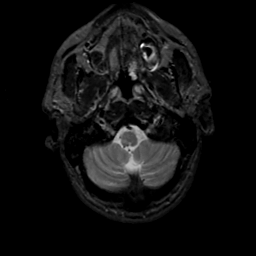

MR Study #15, June 9, 1991 -- Slice #5

[Home][Help][Clinical][Tour 1][Tour 2] Slice 5